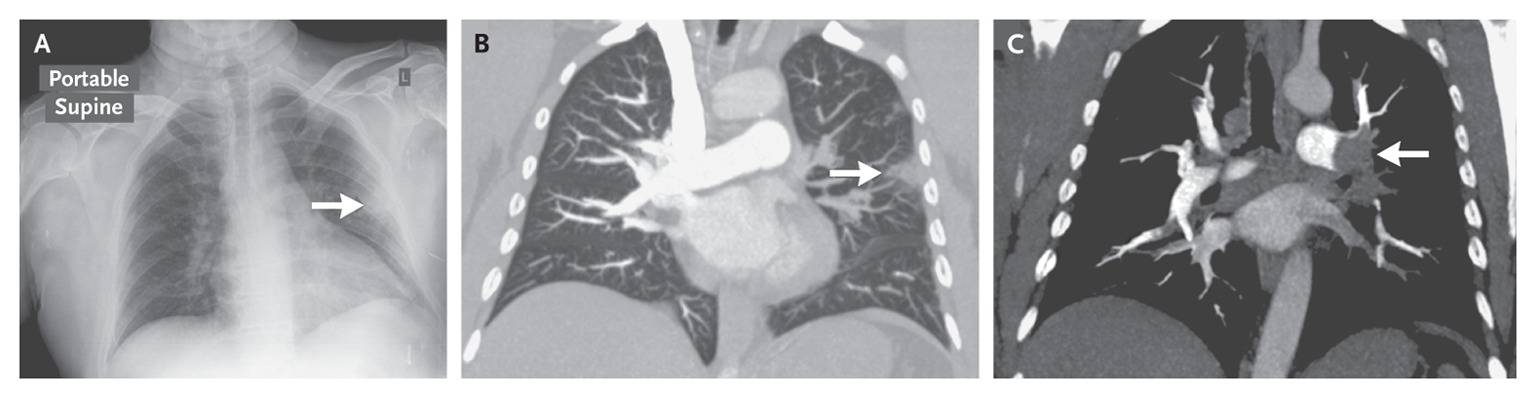

The patient underwent chest radiography, which revealed a Hampton’s hump on the left side of the chest (Panel A, arrow). Computed tomographic pulmonary angiography further defined this area of pulmonary infarction (Panel B, arrow) and revealed bilateral pulmonary emboli, including a thrombus in the left main pulmonary artery (Panel C, arrow).

Originally described in 1940 by Hampton and Castleman, Hampton’s hump is a peripheral wedge-shaped opacification abutting the pleura, signifying pulmonary infarction distal to a pulmonary embolism.